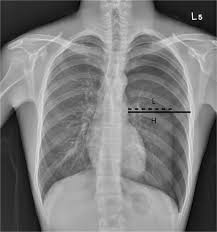

The lungs can be seen to reach the inner edge of the thoracic wall (arrows). Tap on/off image to show/hide findings. Schematic illustration of the radiographic findings and differences between pneumothorax and artifacts related to skinfolds. An occult pneumothorax refers to one missed on initial imaging, usually a supine /semierect chest radiograph 24. This is the one not to miss.

Ultrasound imaging also may be used to identify a pneumothorax. Many observations suggest that spontaneous pneumothorax often results from rupture of a subpleural bleb. Patients with tension pneumothorax usually appear dyspnic and distressed. All patients suspected of having pneumothorax; Pneumothoraces may be small or very large. Tap on/off image to show/hide findings. Pneumothoraces) means the presence of gas (usually air) in the pleural space. If a hemothorax occurs concurrently with a pneumothorax it is then termed a hemopneumothorax. This is the one not to miss. Tap on/off image to show/hide findings. Tap on/off image to show/hide findings. The lungs can be seen to reach the inner edge of the thoracic wall (arrows). Distracting injuries such as fractures or peritonitis were also noted.

Patients with a larger pneumothorax may have decreased movement of the chest wall, a positive coin test result, diminished fremitus, or decreased to absent breath sounds on the affected side. Most individuals with primary spontaneous pneumothorax (psp) have unrecognized lung disease; If a hemothorax occurs concurrently with a pneumothorax it is then termed a hemopneumothorax. The video is an effort to revisit the pneumothorax. Radiographic findings of 2.5 cm air space are equivalent to a 30% pneumothorax. Please see disclaimer on my website www.academyofprofessionals.com Ipsilateral pleural line with reduc ed/absent lung markings (i.e., increased transparency) abrupt change in radiolucency; Schematic illustration of the radiographic findings and differences between pneumothorax and artifacts related to skinfolds. 6 10 supportive findings of pneumothorax. Distracting injuries such as fractures or peritonitis were also noted. Tap on/off image to show/hide findings. Clinical signs of a tension pneumothorax in the ventilated patient are comparably rapid, with arterial and mixed venous peripheral capillary oxygen saturation immediately decreasing 5. A pneumothorax refers to the presence of gas or air in the pleural space.